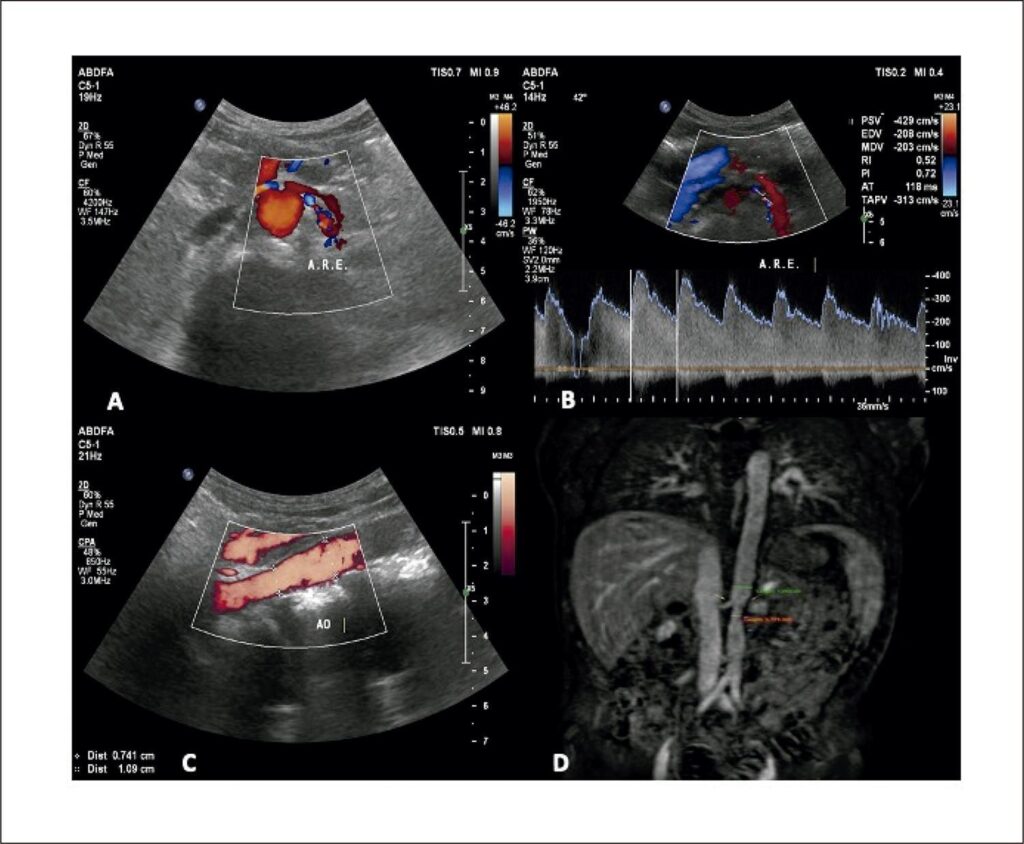

Figure 1

– A) Color flow mapping shows lumen narrowing in the proximal course of the renal artery with flow turbulence; B) spectral Doppler analysis with PSV = 429cm/s and EDV = 208cm/s; C) measurement of the caliber of the abdominal aorta in the path with narrowing = 7.4mm, compared to the most distal path = 10.9mm; D) magnetic angioresonance of the abdominal aorta showing narrowing of the aorta in the path close to the origin of the mesenteric vessels.